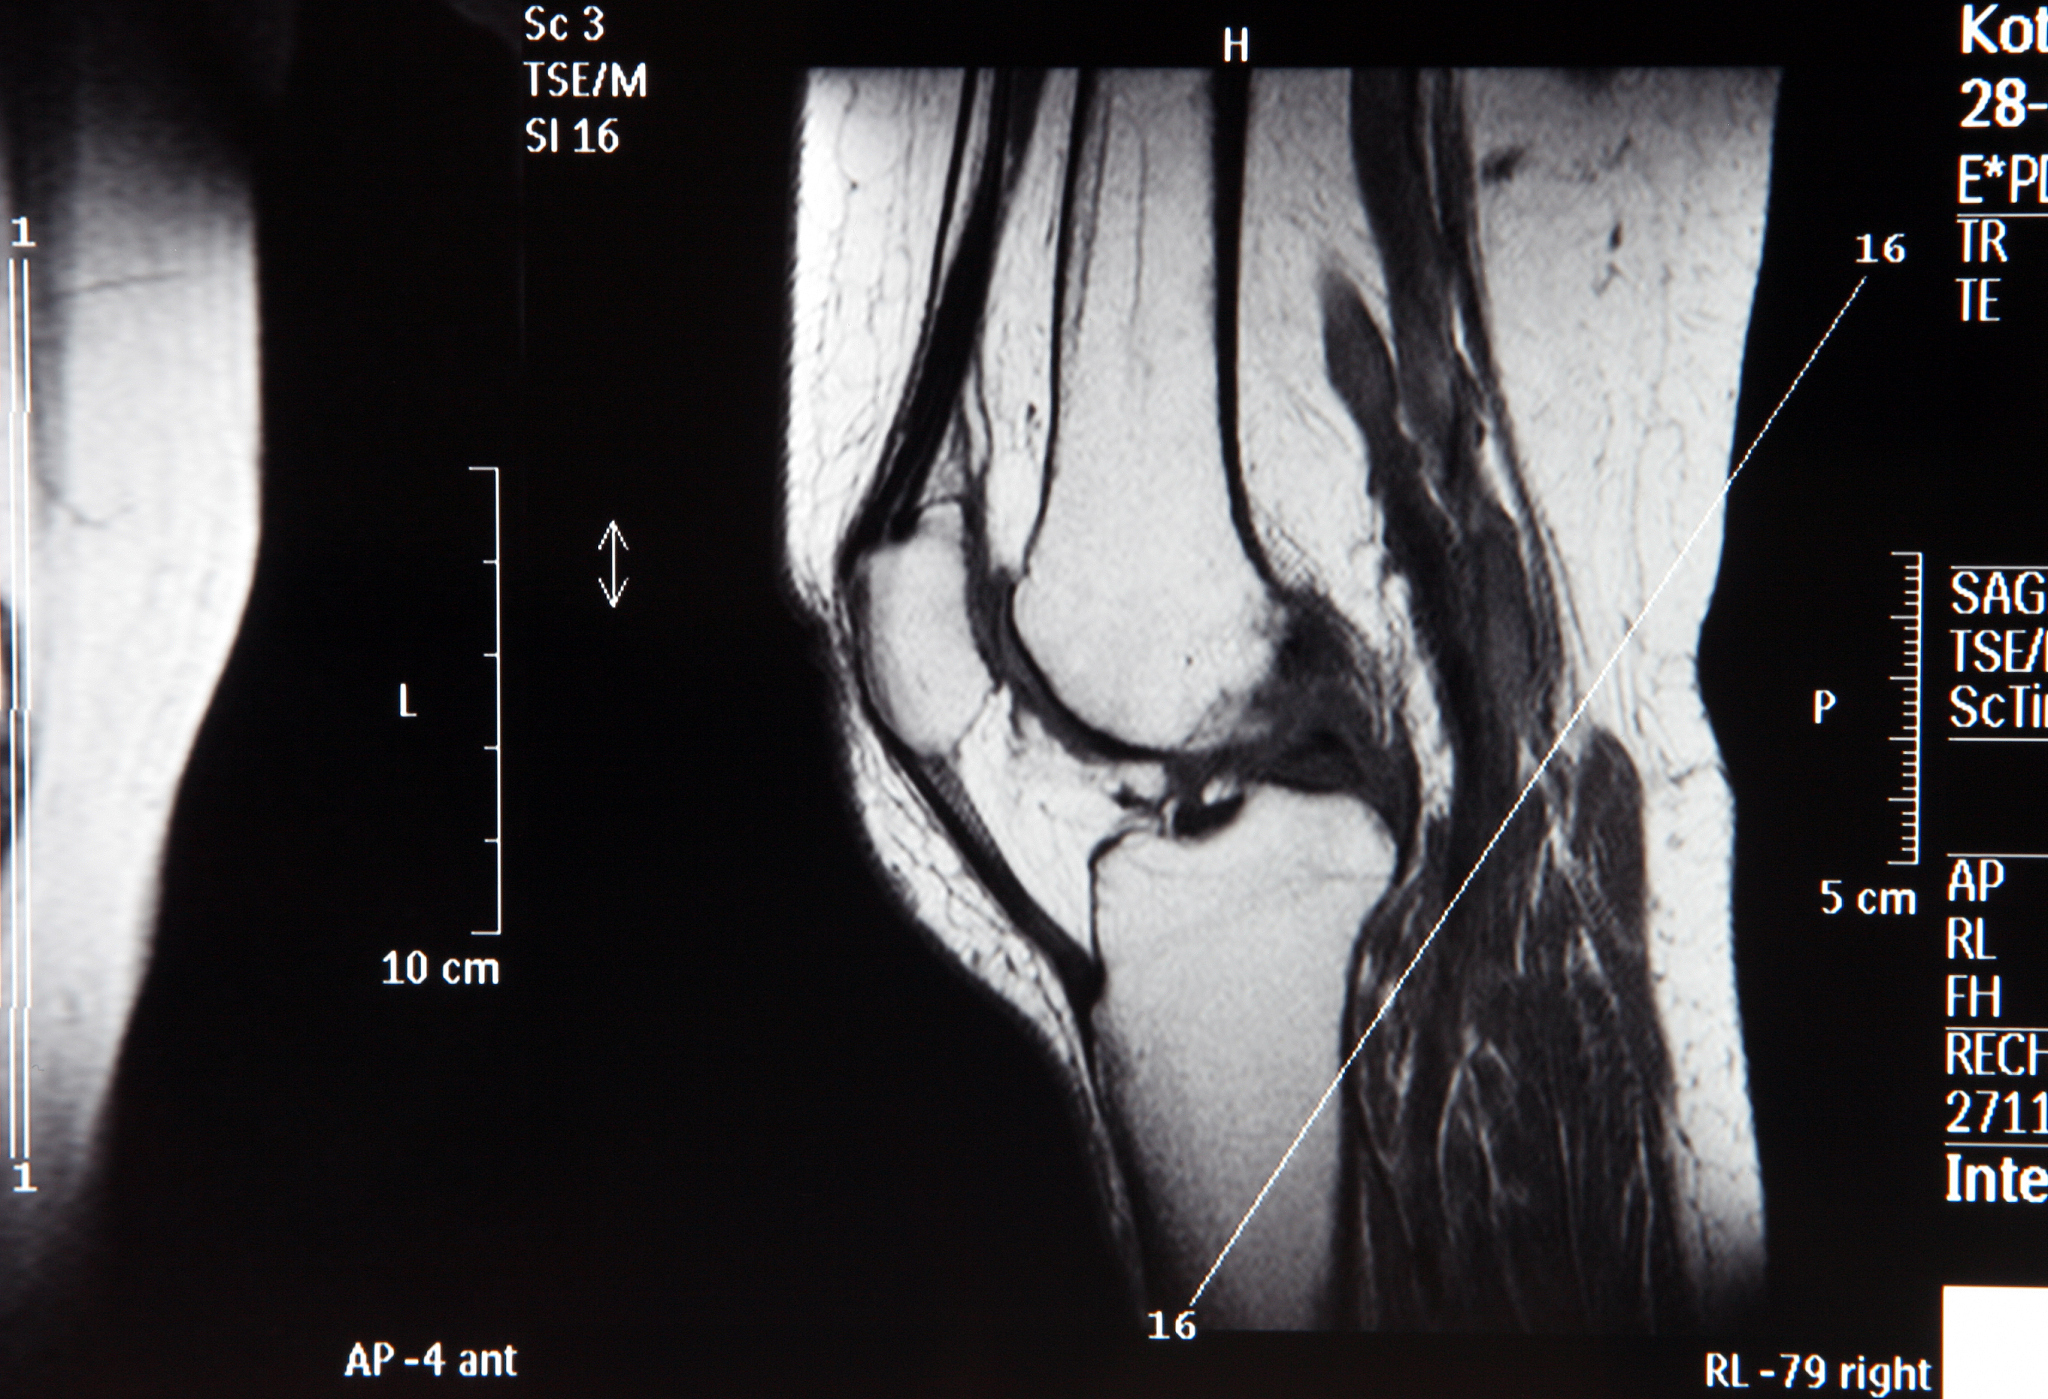

优势方面,南京卫生学校医学影像技术采用了最先进的医学影像设备,如CT、MRI等,可以对患者进行全面、准确的诊断。同时,该学校的医学影像技术团队由一批高素质的医学影像专家组成,他们具有丰富的临床经验和专业知识,能够为患者提供最优质的医疗服务。

技术特点方面,南京卫生学校医学影像技术具有以下几个特点。首先,该技术采用了最先进的医学影像设备,如CT、MRI等,能够对患者进行全面、准确的诊断。其次,南京卫生学校医学影像技术团队由一批高素质的医学影像专家组成,他们具有丰富的临床经验和专业知识,能够为患者提供最优质的医疗服务。最后,医学影像技术还可以为医学研究提供重要的数据支持,有助于推动医学科学的发展。